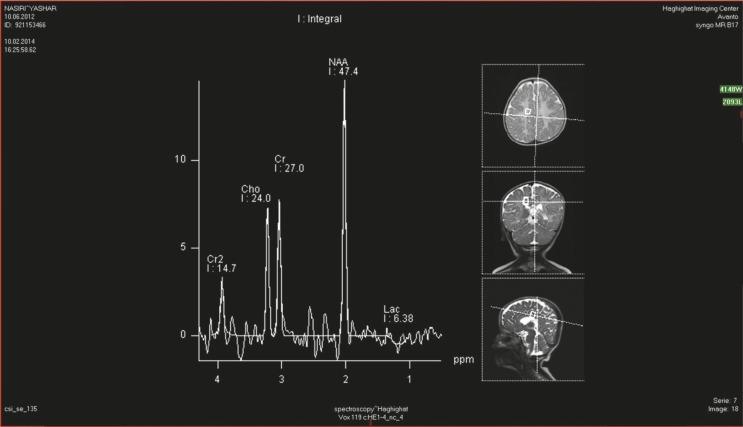

Visual impairment, seizure, hypotonia, neuro developmental arrest, and macrocephaly were the most consistent findings in the patients in this study. Assessments of neuro developmental status revealed that 13 (76%) patients had neuro developmental delays and 4 (24%) patients had normal neuro development until 18 months of age and then their neuro developmental milestones regressed. In this study, 100% of cases had macrocephalia and 76% of these patients had visual impairment. A history of seizures was positive in 8 (47%) patients and began around 3 months of age with the most common type of seizure was tonic spasm. EEGs were abnormal in all epileptic patients. In ten of the infantile group, we did not detect elevated level of N-acetylaspartic acid (NAA) in serum and urine. However, the MRS showed typical findings for Canavan's disease (peaks of N-acetylaspartic acid).

We suggest using MRS to detect N-acetylaspartic acid as an acceptable method for the diagnosis of Canavan's disease in infants even with normal serum and urine N-acetylaspartic acid levels.

视力障碍、癫痫发作、肌张力减退、神经发育停滞和巨头畸形是本研究患者中最常见的表现。神经发育状况评估显示,13名(76%)患者存在神经发育迟缓,4名(24%)患者在18个月大之前神经发育正常,之后其神经发育里程碑出现倒退。在本研究中,100%的病例有巨头畸形,其中76%的患者有视力障碍。8名(47%)患者有癫痫发作史,发作始于3个月左右,最常见的发作类型是强直性痉挛。所有癫痫患者的脑电图均异常。在婴儿组的10名患者中,我们未检测到血清和尿液中N - 乙酰天门冬氨酸(NAA)水平升高。然而,MRS显示出卡纳万病的典型表现(N - 乙酰天门冬氨酸峰)。

我们建议使用MRS检测N - 乙酰天门冬氨酸,即使血清和尿液中N - 乙酰天门冬氨酸水平正常,这也是诊断婴儿卡纳万病的一种可接受方法。